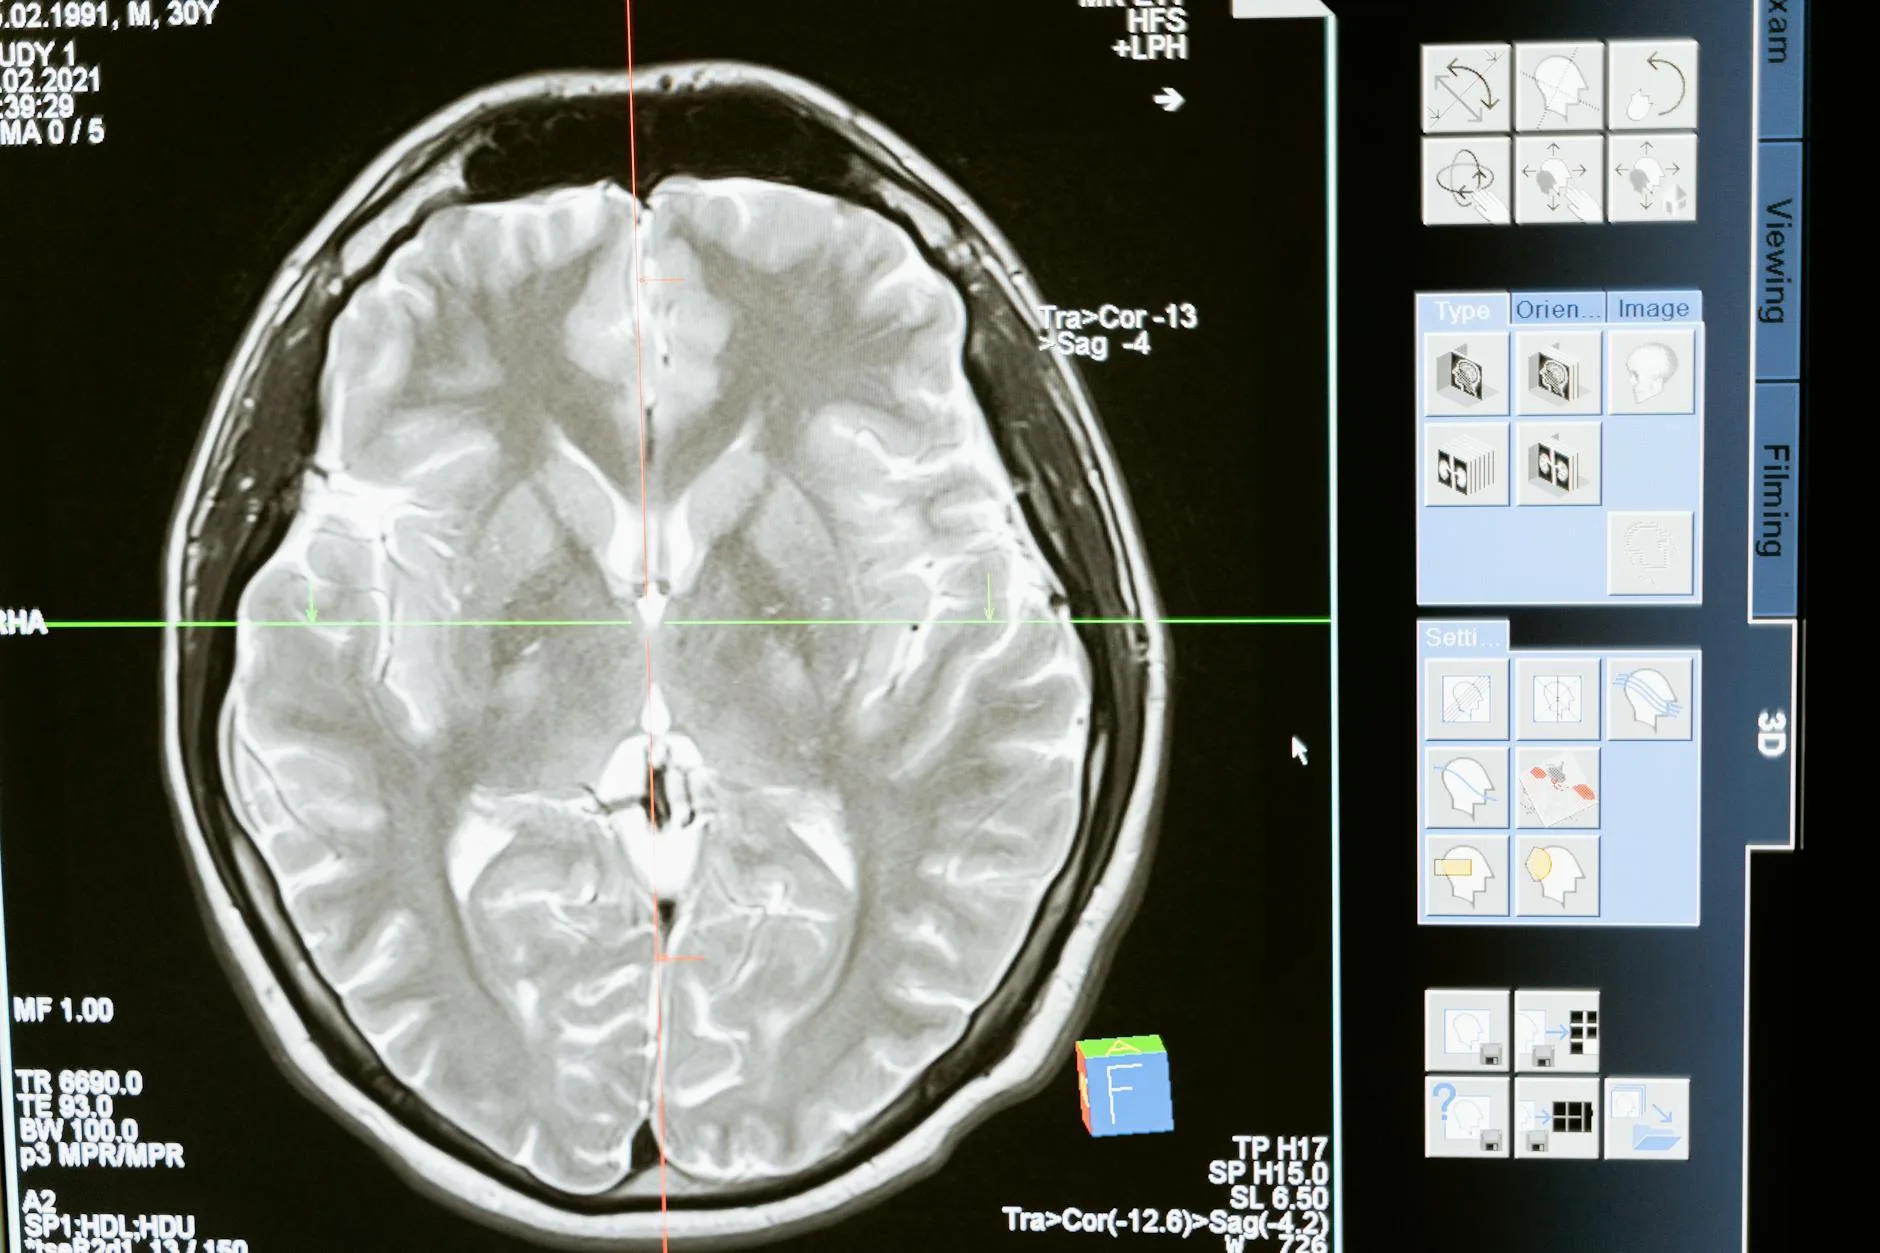

Kliniğimizde HINTS’i sistematik uyguluyoruz. Kombinasyonda santral düşündüren her bulgu için MRI difüzyon çekilir.

- MRI difüzyon — santral şüphede standart

MRI ne zaman gerekli?